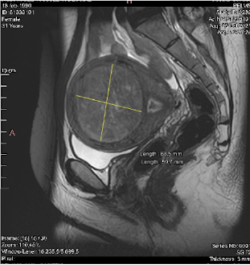

- La mida i la localització dels miomes (vegeu classificació de la FIGO)

De fet, tots els miomes de 0 al 6 són candidats a la radiofreqüència.